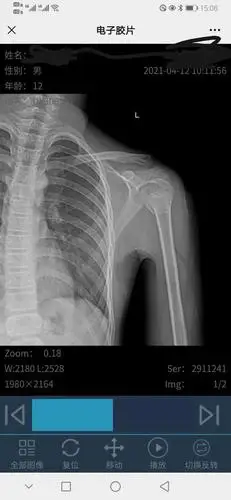

孩子摔伤,左肱骨近端骨折,是保守治疗还是动手术治疗好

骨骼x线诊断 正常肱骨

肱骨干骨折

肱骨近端骨折:解剖,分型,治疗及内固定全面讲解!

左侧肱骨髁上骨折一例